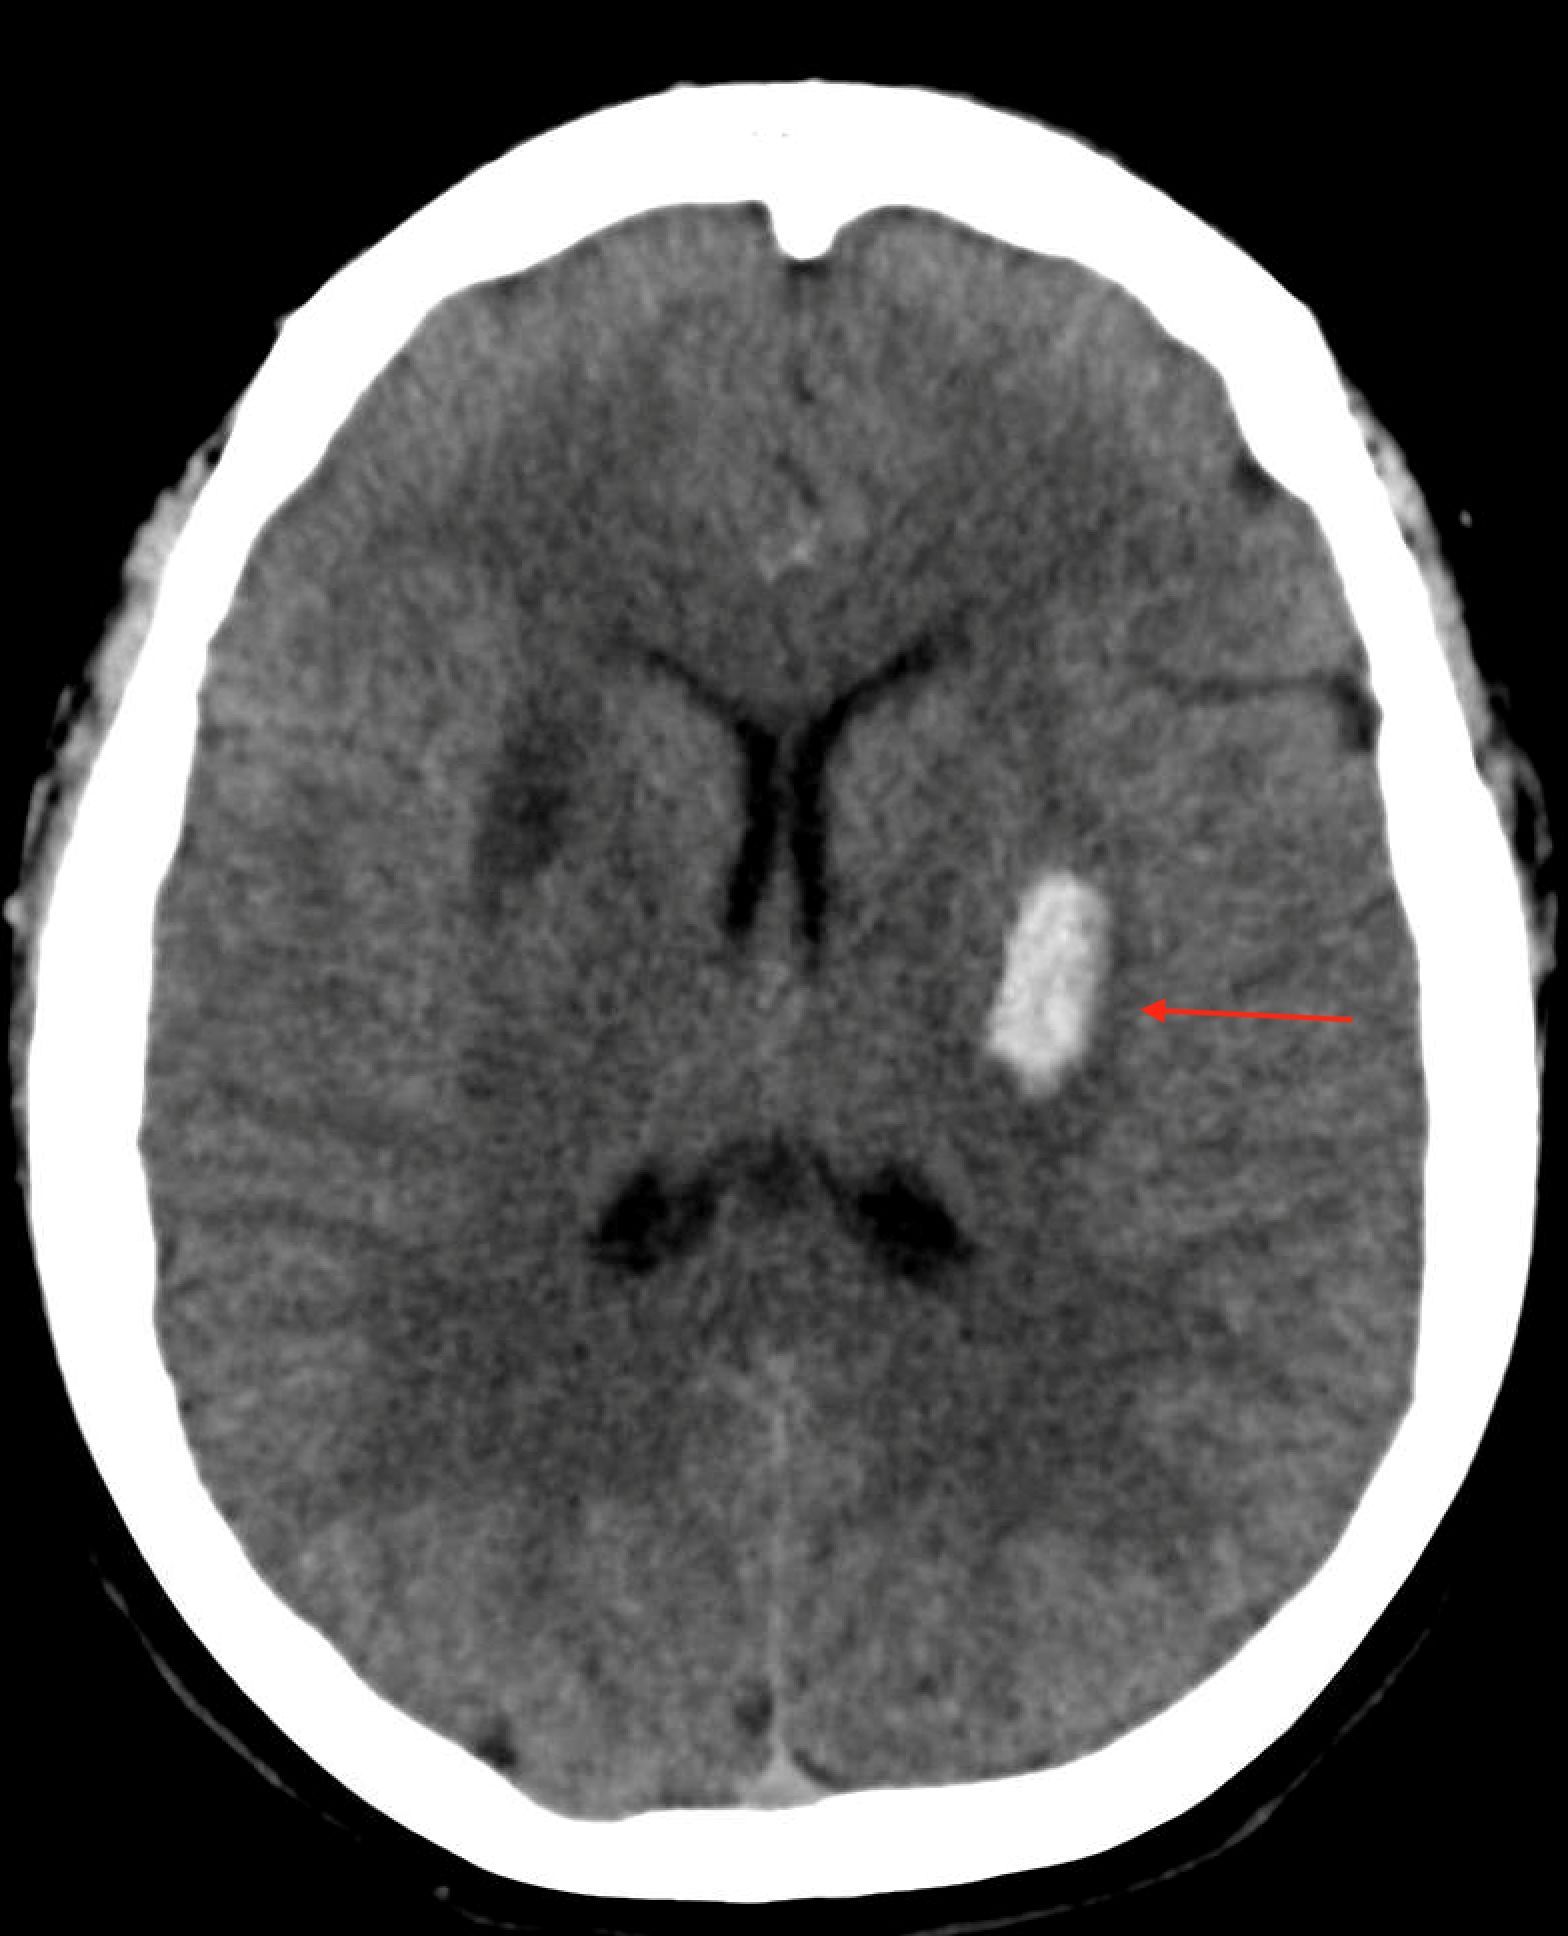

Intravenous alteplase (tPA) is the standard of care for acute ischemic stroke, if it can be given within 3-4.5 hours after stroke onset. Dr. Wilner reviews some important facts about intracranial hemorrhage after the use of intravenous alterpase.